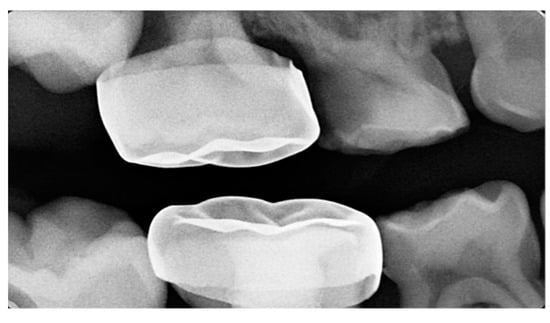

| Harrison and Michal’s Classification (based on severity of the lock using bitewing radiograph) * | |||||

| Normal | Minimal lock | Severe lock | |||

| No sign of impaction | Impacted less than half the width of the distal marginal ridge of the second primary molar | Impacted more than the width of the distal marginal ridge of the second primary molar | |||

![]() | ![]() | ![]() | |||